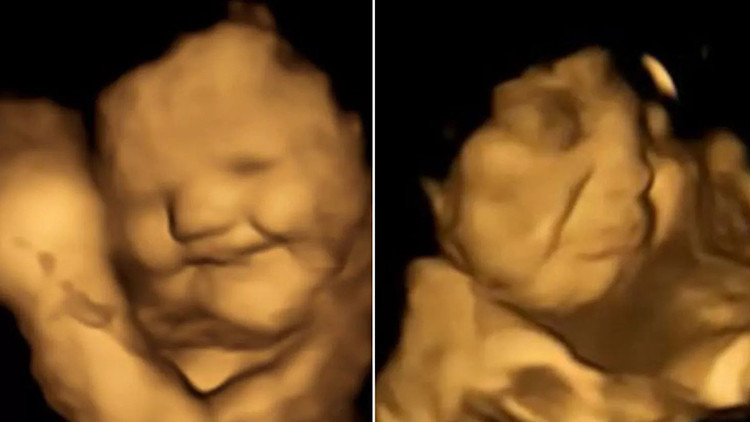

Durham Üniversitesi’nden araştırmacılar, 100 hamile kadının 4D ultrason taramalarını inceleyerek, doğmamış bebeklerin annelerinin yediği yiyeceklerin tatlarına nasıl tepki verdiklerini inceledi. Sonuçlar oldukça ilgi çekiciydi: Fetüsler anneleri havuç yedikten kısa bir süre sonra gülümserken, anneleri karalahana tercih ettiğinde yüzlerini buruşturuyordu.

Sonuçları Psychological Science dergisinde yayımlanan araştırma, az miktarda havuç veya karalahana aromasının bile fetüslerde reaksiyona sebep olduğunu ortaya koydu. Fetüsler anneleri havuç tükettiklerinde gülümseme eğilimindeyken, karalahana tükettiklerinde yüzlerini buruşturuyorlardı.

Araştırmanın başyazarı Beyza Üstün, "Doğmamış bebeklerin taramalar sırasında lahana ya da havuç aromalarına verdikleri tepkileri görmek ve bu anları ebeveynleriyle paylaşmak gerçekten inanılmazdı. Sonuç olarak, doğumdan önce tatlara tekrar tekrar maruz kalmanın, doğum sonrası gıda tercihlerinin belirlenmesine yardımcı olabileceğini düşünüyoruz” dedi.